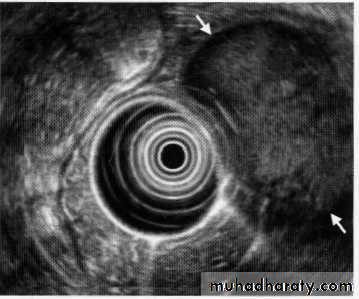

Leiomyoma EUS